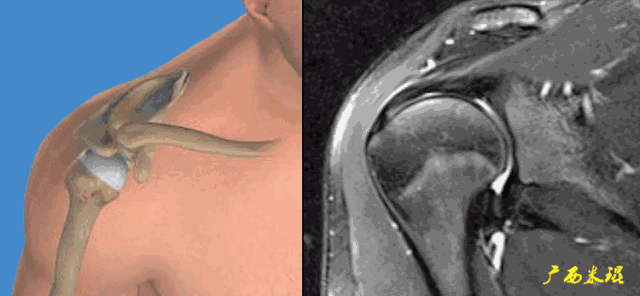

1、斜冠状位:平行于冈上肌腱长轴,主要评估冈上肌。

2、斜矢状位:垂直于冈上肌长轴,观察肩峰形态及喙肩弓,观察肩袖4个组分的短轴断面。

3、轴位:平行于关节盂/垂直于盂肱关节,主要评估盂唇,同时兼顾肩胛下肌、冈下肌及小圆肌。